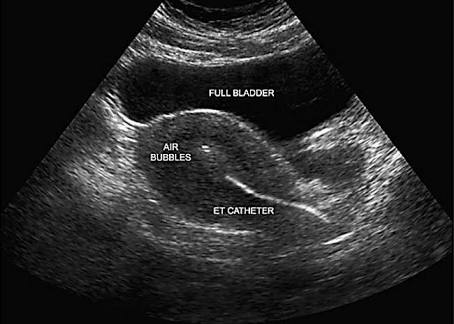

Embryo transfer

S.S.G(सोनोसालफिंगोग्राफी) गर्भाशयात विशिष्ट प्रकारचे औषध सोडून सोनोग्राफीच्या साहाय्याने गर्भाशय व नळयाची तपासणी